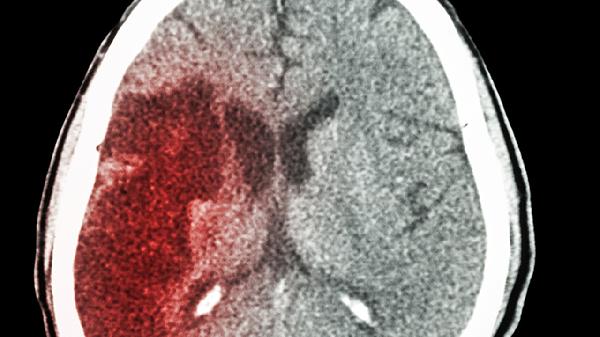

脑出血开颅手术在急诊救治中具有关键作用。对于基底节区、脑叶等非脑干部位出血,且出血量在30-50毫升的患者,手术清除血肿能显著降低颅内压,术后配合脱水降颅压、控制血压等治疗,患者神经功能恢复概率较高。若患者术前意识障碍较轻,无严重基础疾病,术后存活率可达较高水平。手术时机对预后影响显著,发病后6小时内实施手术效果更佳。

脑干出血或出血量超过60毫升的广泛出血患者手术风险显著增加。这类患者常伴随深度昏迷、脑疝等危重情况,术后可能出现呼吸循环衰竭、多器官功能障碍等并发症。高龄、合并高血压糖尿病等慢性病患者术后恢复难度更大,需长期康复治疗。部分患者术后可能遗留偏瘫、失语等神经功能缺损。